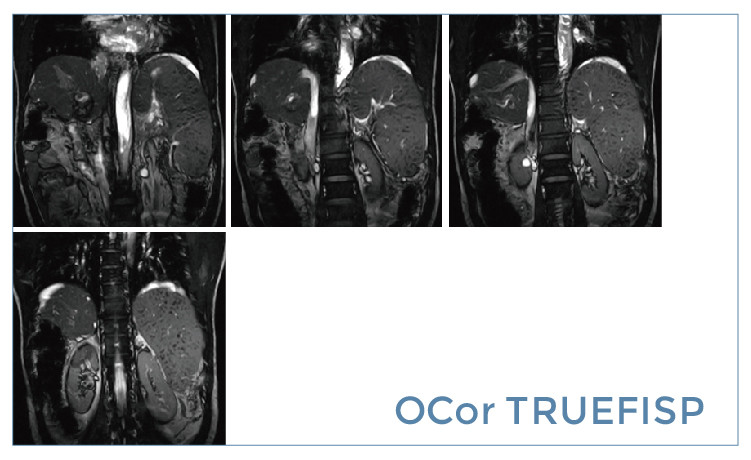

朗润影像档案】磁共振影像病例分享(编号20190517)